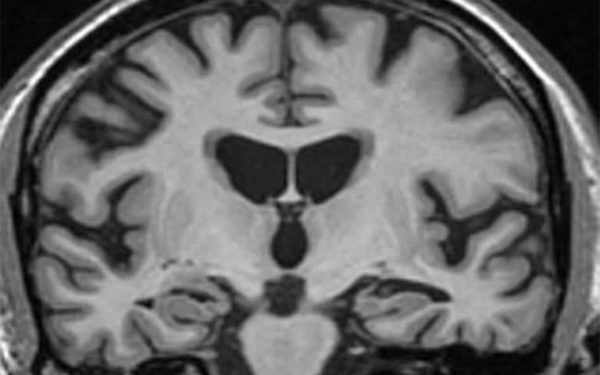

Neuroinflammatory diseases, including Alzheimer’s disease and traumatic brain injury, have been linked to deposits of a tough protein known as fibrin, derived from the blood clotting factor fibrinogen. These mesh-like fibrin deposits occur outside blood vessels in the brain, contributing to the death of certain central nervous system cells (neurons) that eventually leads to impaired memory.

Dr. Lominadze and others have shown that inflammatory disease is associated with a higher concentration of fibrinogen in the blood, increased generation of potentially damaging free radicals, neuronal cell activation and microvascular permeability. In previous studies using their mouse model for mild-to-moderate traumatic brain injury, Dr. Lominadze’s group reported that fibrinogen after crossing the vascular wall accumulated in spaces between the microvessels and astrocytes (another brain cell type connecting vessels and neurons) and activated the astrocytes. This activation coincided with increased neurodegeneration and reduced short-term memory.